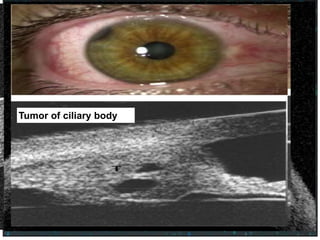

Tumor of the iris

Obscuring the angleTumor of ciliary body

A study comparing AS-OCT with Goniscopy